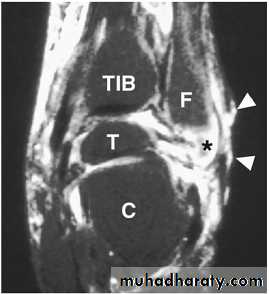

Magnetic resonance imaging (MRI) is the most specific

and sensitive non-invasive test to evaluate

Osteomyelitis

probable abscess

sinus tract formation.